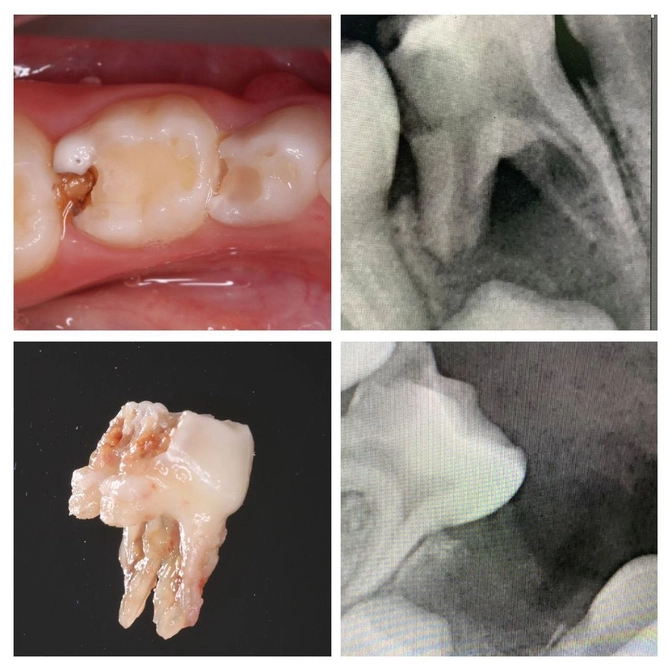

Родители заметили на десне "прыщик" как раз под зубом вот с таким небольшим разрушением.

Сделали снимок и видим, что воспаление уже полностью захватило зуб и угрожает зачатку постоянного.

Оно уже ушло вглубь и перешло на соседние ткани - периодонт.

Диагноз - периодонтит молочного зуба.

Именно из-за него на десне вылез свищ.

Под местной анестезией "четверка" была удалена.